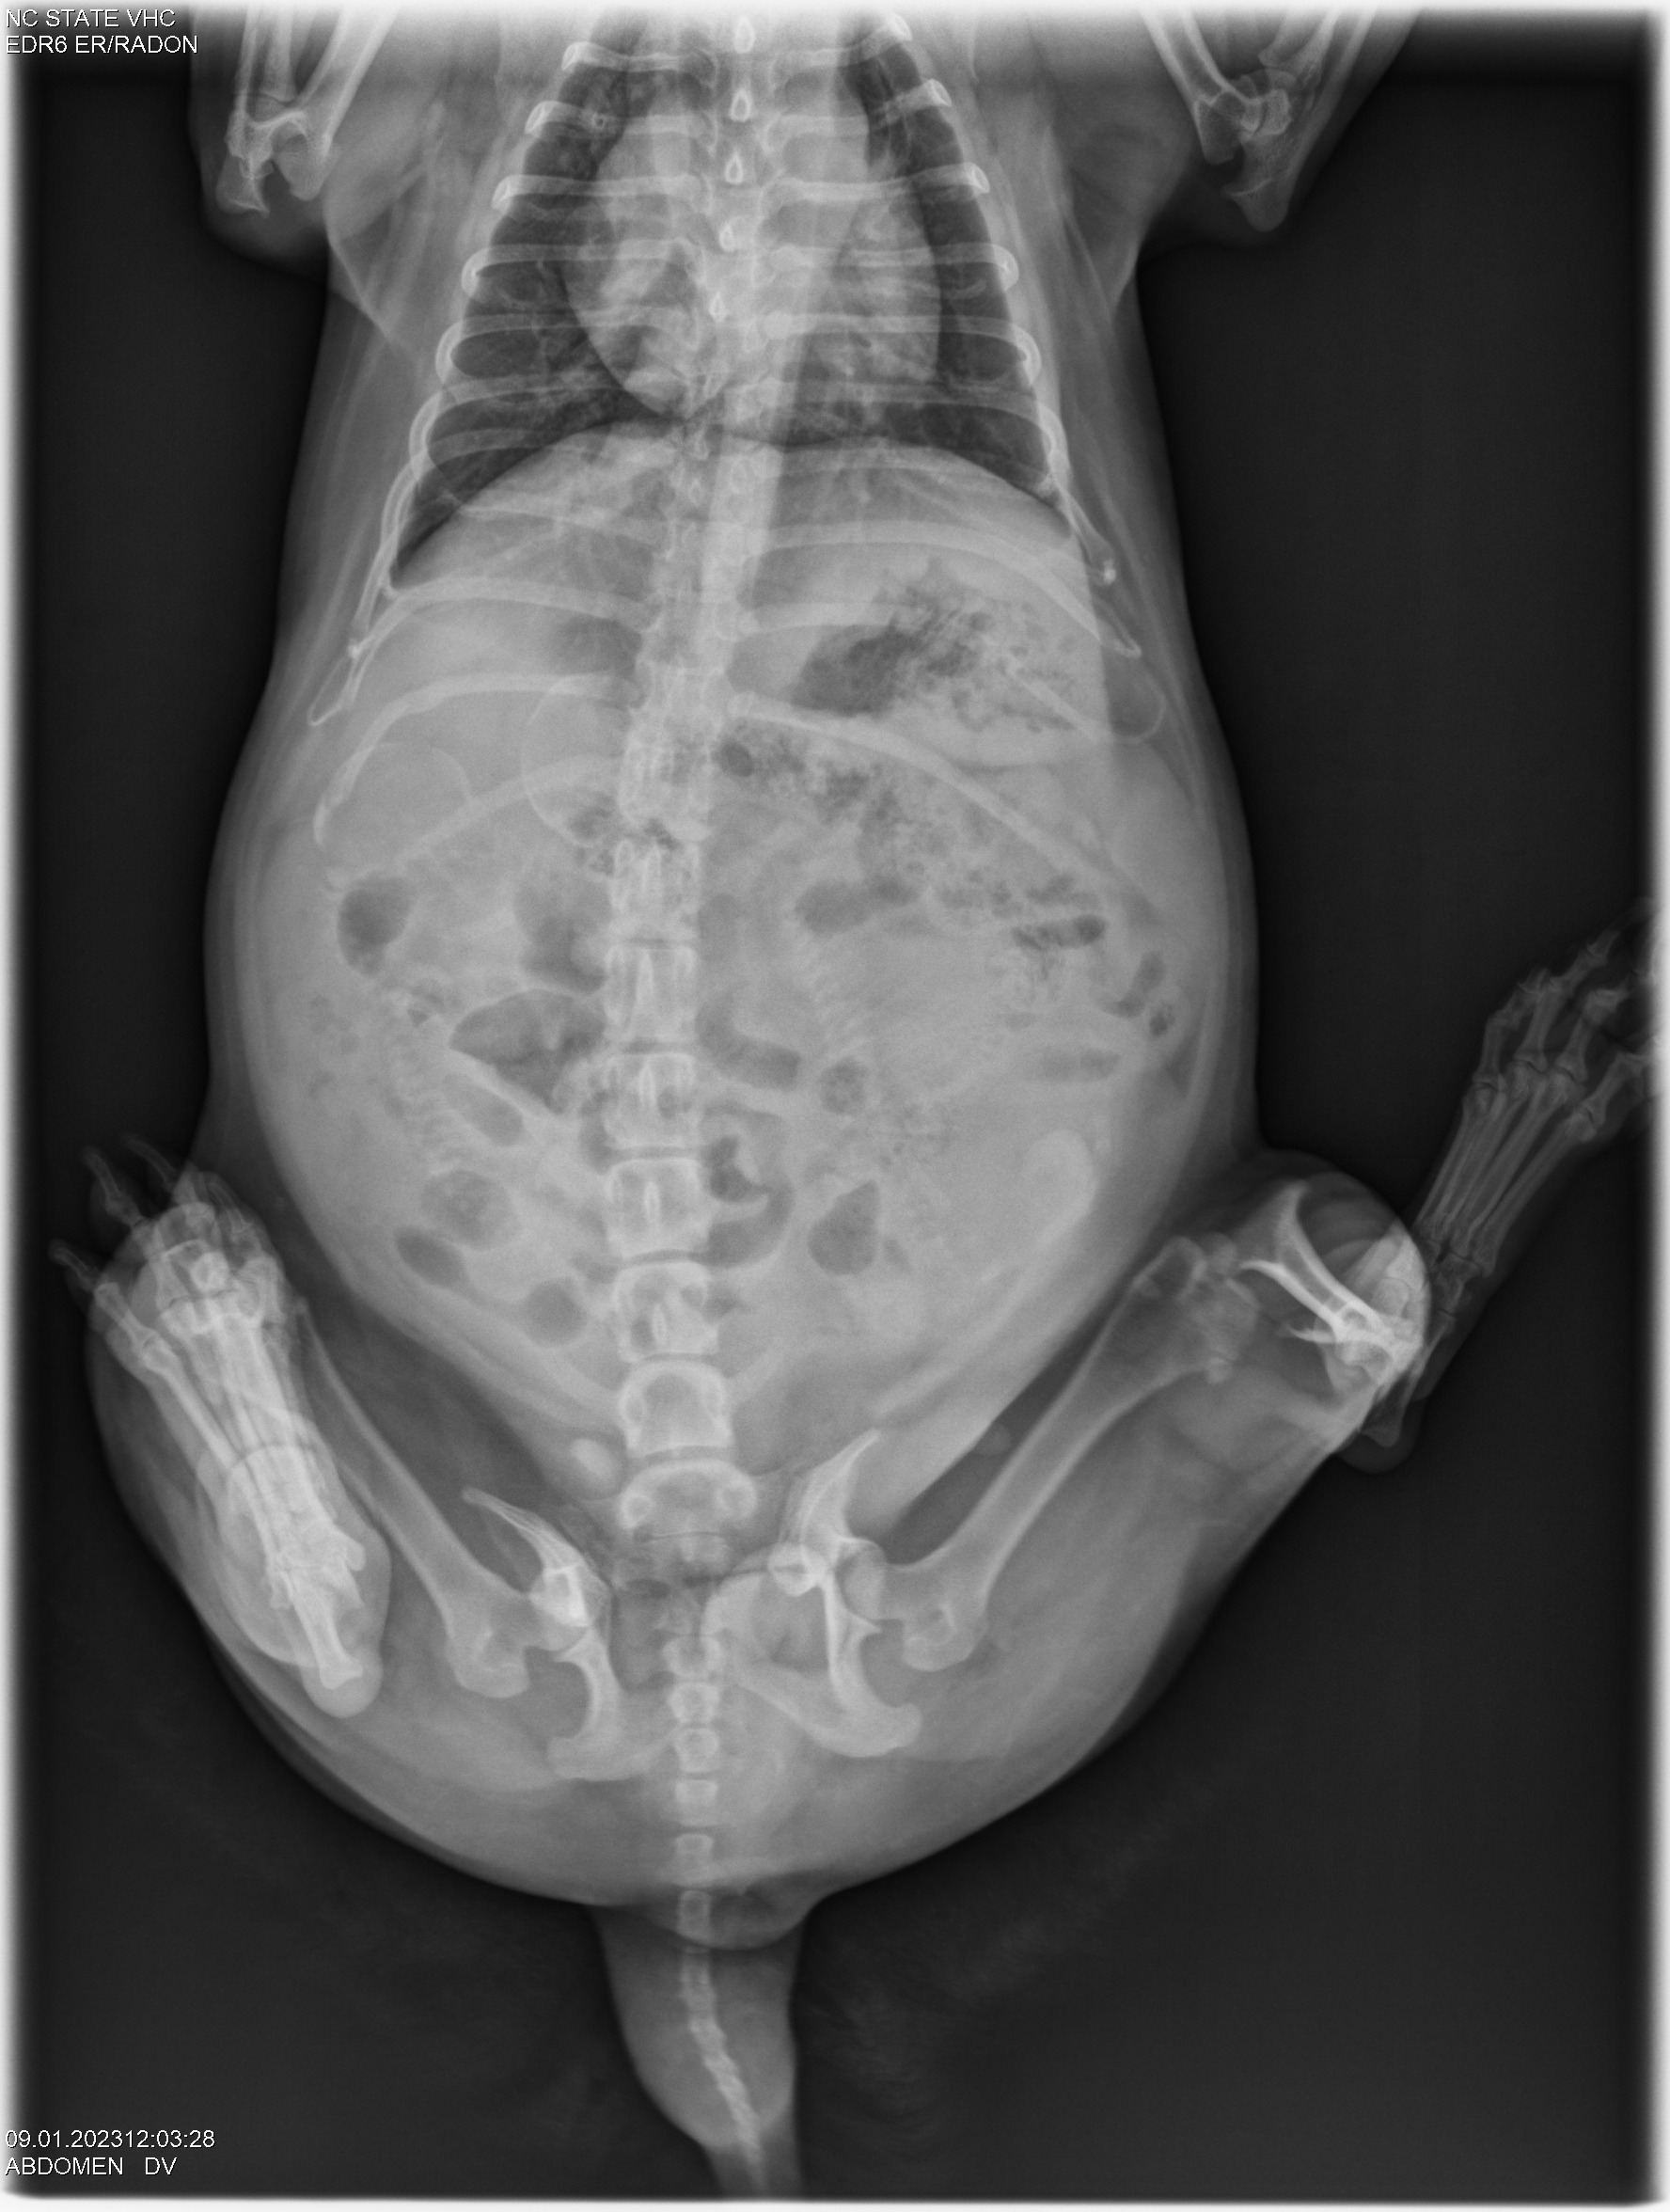

Today was x-ray day! I took both Gwynie and Siri to NC State University for abdominal x-rays. Here they are: (If you look closely, you can see the spines and perhaps the skulls of the puppies.)

Looking at the x-rays, my repro vets told me that Gwynie is carrying three puppies, and Siri is carrying two. Comparing the size of the pelvic opening of each girl with the size of the puppy skulls they are carrying, I was told for both Gwynie and Siri that the sizes are close. I was advised to have a cesarean section (c-section) for both girls. So that is what we will do.

Since Gwynie's due date is this weekend, the vets started "staging" Gwynie for a c-section. The vets checked out Gwynie's puppies using ultrasound and all looks good - good heartbeats and good GI motility. They took some blood from Gwynie and did a progesterone test. Towards the end of pregnancy, progesterone falls. Using the ultrasound results and progesterone number lets the vets decide when to do a c-section. Gwynie and I will now come back to NC State (a two-hour ride one-way) each morning for progesterone testing and ultrasound until the vets say "today is the day" for the c-section.